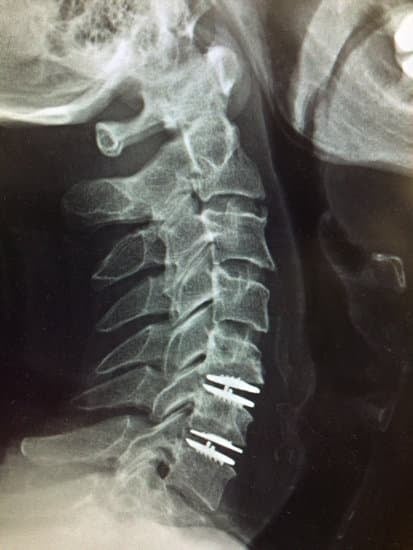

인공 디스크 치환술(Artificial Disc Replacement, ADR)은 척추의 손상된 디스크를 인공 디스크로 교체하여 척추의 운동성과 기능을 회복하는 수술입니다.

디스크 삽입: 인공 디스크는 금속과 플라스틱 소재로 만들어지며, 이 디스크를 척추 사이에 삽입하여 척추의 기능을 대체합니다.